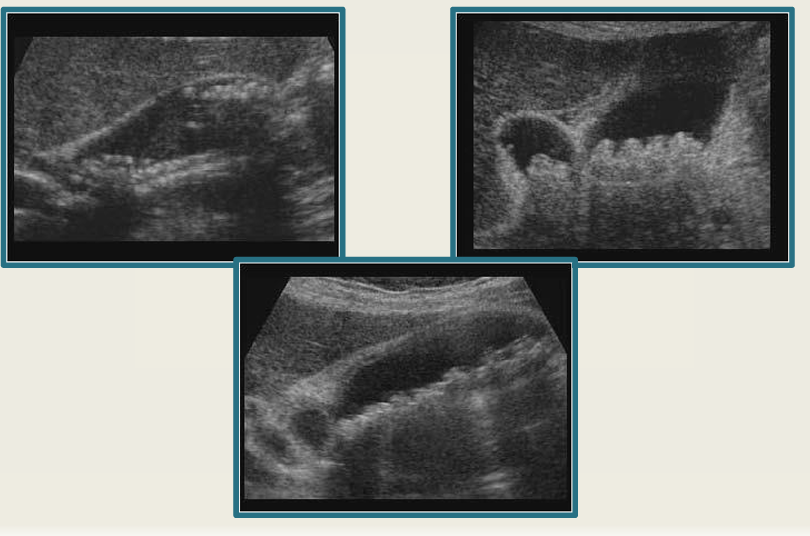

9

New cards

term image

cholecystitis

10

gangrenous GB

11

emphysematous cholecystitis

12

GB perforation